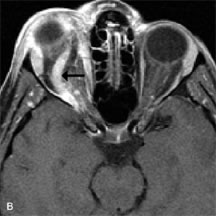

Extraocular muscle enlargement in patients with thyroid-associated orbitopathy is demonstrated equally well with CT and MRI studies. However, the superior tissue contrast on MR images reveals better details of the relationships of the optic nerve to the thickened muscles at the orbital apex (Fig. 16).50 In addition, MRI may be able to differentiate between muscles that are enlarged as a result of edema and active inflammation and those enlarged because of fibrosis by their T2 relaxation times.21 Quantitative MRI was not found to be accurate in predicting the success of low-dose orbital irradiation.51 However, a muscular index relating the diameters of the rectus muscles to the bony orbital dimensions was useful in predicting optic nerve compression.52

Fig. 16. A-C, T1-weighted MR scans obtained with a high-resolution surface coil demonstrate fusiform enlargement of the extraocular muscles. The medial, lateral, and inferior rectus muscles are especially involved. Note the relative sparing of the tendinous insertions, a finding characteristic of this disease process, as well as fatty infiltration of the lateral and inferior rectus muscles. There is marked proptosis, best visualized on the sagittal image (A), and mild crowding of the optic nerve at the orbital apex.